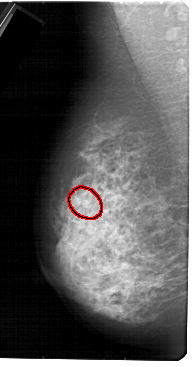

A_1531_1.LEFT_MLO

LEFT_MLO LINES 5491 PIXELS_PER_LINE 2866 BITS_PER_PIXEL 12 RESOLUTION 43.5 OVERLAY

FILE: A_1531_1.LEFT_MLO.OVERLAY

TOTAL_ABNORMALITIES 1

ABNORMALITY 1

LESION_TYPE CALCIFICATION TYPE PLEOMORPHIC DISTRIBUTION CLUSTERED

ASSESSMENT 4

SUBTLETY 4

PATHOLOGY MALIGNANT

TOTAL_OUTLINES 1